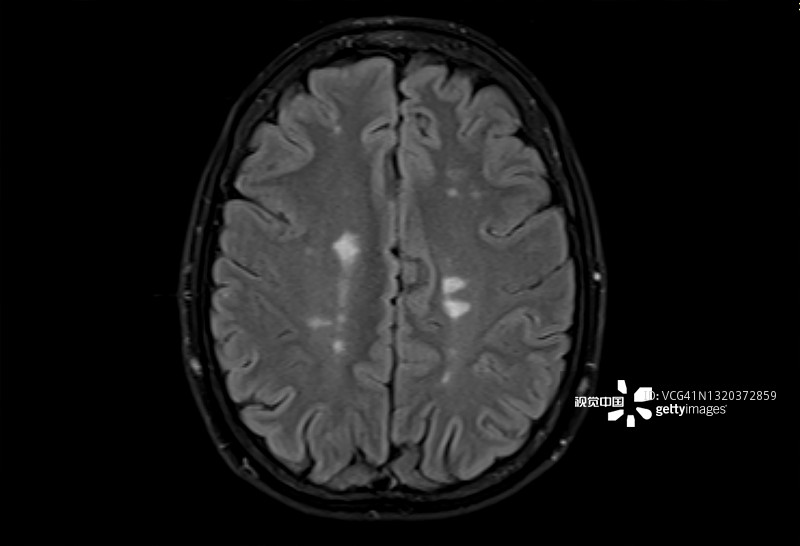

多發(fā)性腦硬化癥的磁共振成像,軸位Flair視圖

多發(fā)性硬化癥 (MS)MS是一種中樞神經(jīng)系統 (CNS) 的慢性自身免疫和炎癥性疾病。MS與免疫系統介導的自身反應性T細胞和B細胞對神經(jīng)元髓鞘的攻擊有關(guān),導致脫髓鞘并最終導致神經(jīng)元丟失。由于中樞神經(jīng)系統中神經(jīng)變性和斑塊的形成,MS患者會(huì )根據斑塊的位置經(jīng)歷特定的神經(jīng)功能障礙。例如,視神經(jīng)中的斑塊會(huì )導致視力喪失。